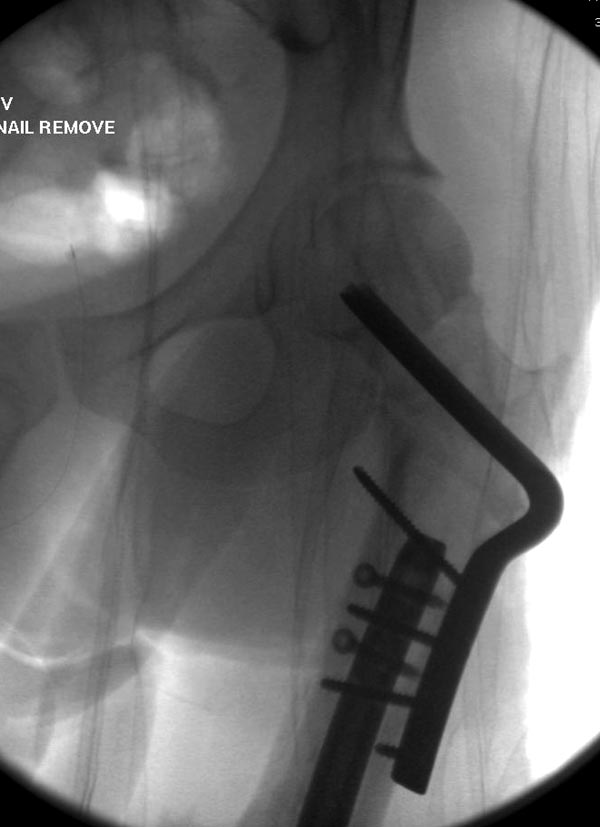

Здесь выставлен ренгенограммы больного, ему 21, травму получил в

результате высокоскоростной погони на украденной машине, которая

закончилась смертью трех остальных“боевых комрадов”. Начатую коллегой

открытую операцию на шейке пришлось закончить мне, установкой винтов и

ретроградной фиксацией бедра. Выписка в обычное сроки и наблюдался

амбулаторно. Каждый раз напоминали о возможности осложнений ввиде

несращения! По истечению 4 месяцев появились признаки варусной

деформации. На СТ срезах несращение шейки и бедра. Риминг, замена на

более толстый гвоздь и вальгусная остеотомия.